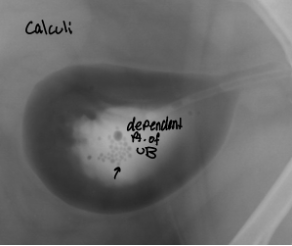

double contrast cystography highlights

mural diseases and intramural filling defects

intraluminal filling defects

3 types of free intraluminal defects bladder

calculi

hematoma, blood clot

gas bubbles

5 etiologies that can distort bladder content

bladder

sandy calculi